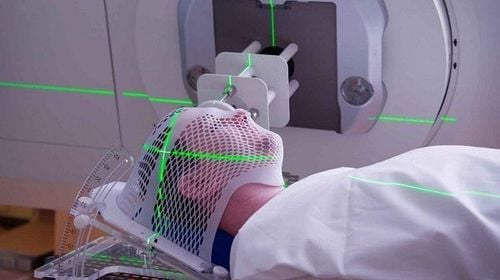

- Xạ trị ung thư

Bằng cách sử dụng bức xạ năng lượng cao, xạ trị tiêu diệt các tế bào ung thư bằng cách làm hỏng DNA của chúng. Việc điều trị này cũng có thể làm tổn hại đến các tế bào bình thường.

Để loại bỏ hoàn toàn các electron khỏi các nguyên tử và phân tử, các bức xạ ion hóa từ tia X chiếu vào một khu vực tập trung có đủ năng lượng, do đó làm thay đổi tính chất của chúng.

Điều này có thể làm hỏng hoặc phá hủy các tế bào nếu ở mức thích hợp. Nó cũng cũng có thể được sử dụng để chống lại nó trong trường hợp những tổn thương tế bào này có thể gây ung thư. Nó có thể phá hủy những tế bào bất thường đó bằng cách hướng tia X vào các khối u ác tính.

Tia X ngày nay được sử dụng phổ biến trong lĩnh vực y tế để điều trị ung thư. Viện Ung thư Quốc gia Mỹ khuyến cáo việc điều trị nên được lên kế hoạch cẩn thận nhằm giảm thiểu tác dụng phụ vì tia X cũng phá hỏng các tế bào bình thường.